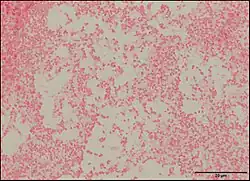

Pseudescherichia vulneris is a Gram-negative bacterial species. P. vulneris is a fermentative, oxidase-negative, motile rod, which holds characteristics of the family Enterobacteraceae. This bacterium can colonize in the respiratory tract, genital tract, stool, and urinary tract. However, P. vulneris is most often associated with wounds and has been known to colonize open wounds of both humans and animals. This association gave the bacterium its species name, vulneris, which is Latin for wound. It has also been infrequently reported in cases of meningitis. It was identified as Escherichia vulneris in 1982 with a 2017 genomic analysis of its original genus resulting in the creation of its new genus Pseudescherichia.[1][2]

Morphology